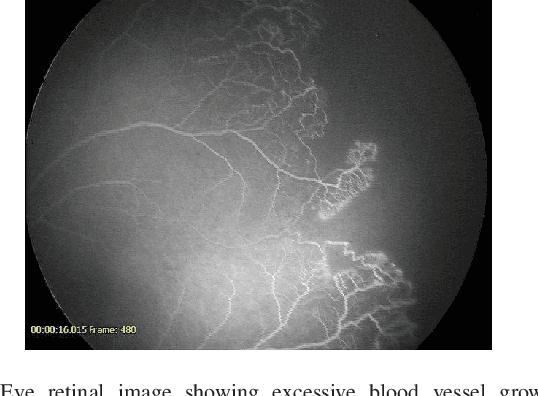

Deep Learning Methods for Retinal Blood Vessel Segmentation: Evaluation on Images with Retinopathy of Prematurity

Figure 1 for Deep Learning Methods for Retinal Blood Vessel Segmentation: Evaluation on Images with Retinopathy of Prematurity

Figure 2 for Deep Learning Methods for Retinal Blood Vessel Segmentation: Evaluation on Images with Retinopathy of Prematurity

Figure 3 for Deep Learning Methods for Retinal Blood Vessel Segmentation: Evaluation on Images with Retinopathy of Prematurity

Figure 4 for Deep Learning Methods for Retinal Blood Vessel Segmentation: Evaluation on Images with Retinopathy of Prematurity